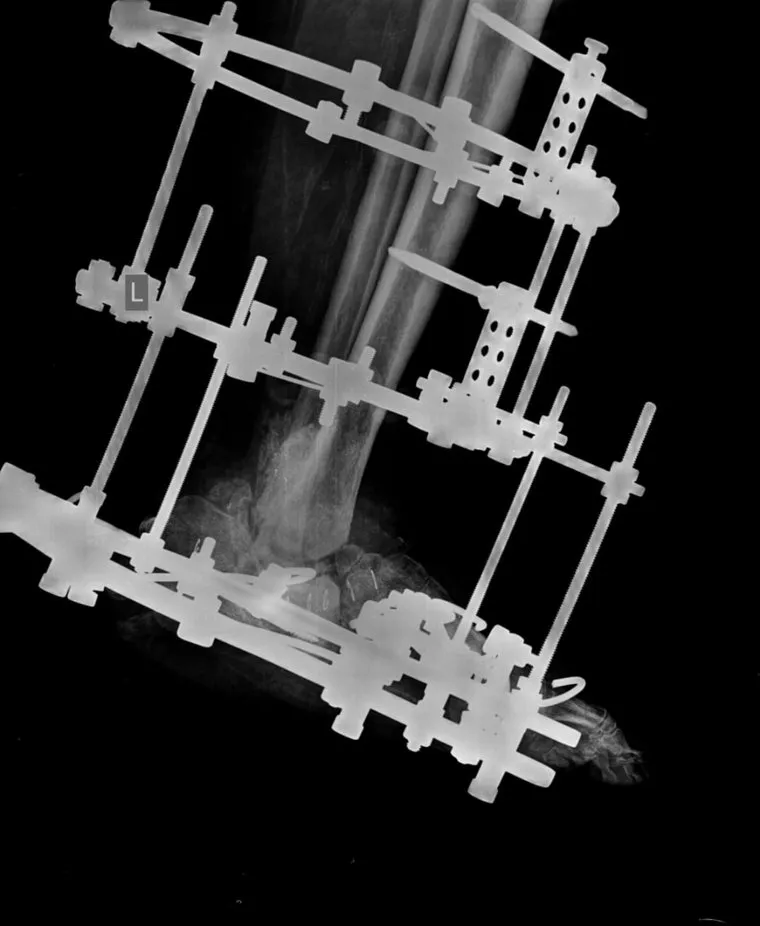

В Центре Илизарова в Кургане врачи спасли стопу 64-летнего пациента из Омана, страдающего диабетической стопой Шарко. В других клиниках мужчине предлагали ампутацию. Благодаря использованию усовершенствованного аппарата Илизарова и методу чрескостного остеосинтеза удалось сохранить ногу, рассказали в пресс-службе медицинского учреждения.

«64-летний пациент из Омана приехал в Курган с надеждой сохранить конечность. На фоне сахарного диабета у него развилось ортопедическое осложнение — нейроостеоартропатия, больше известное как диабетическая стопа Шарко. Его мучила обширная незаживающая рана на левой стопе. В Центре Илизарова жителя Омана госпитализировали в гнойное травматолого-ортопедическое отделение №2. Операцию провел заведующий научной лабораторией Клиники костно-суставной инфекции Анатолий Судницын», — сообщили в Центре.

В иностранных клиниках мужчине предлагали ампутацию больной стопы, тогда он обратился в Центр Илизарова, пользуясь ресурсами телемедицины

Фото: «НМИЦ ТО им. акад. Г.А. Илизарова Минздрава РФ»

Курганские врачи проконсультировали пациента дистанционно, а через некоторое время он приехал из Омана в Курган на операцию